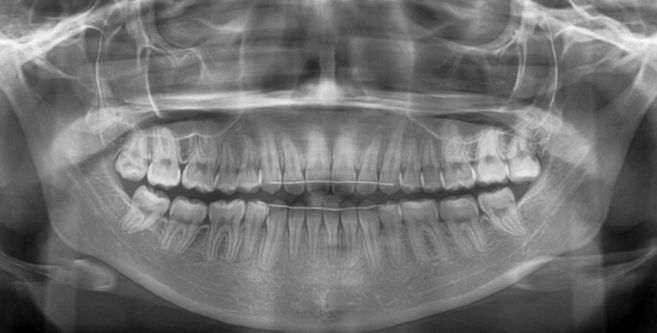

| 年齢・性別 | 15歳の女性 |

|---|---|

| 主訴 | 咬み合わせが逆であること(反対咬合)を気にされて来院された15歳7か月の女性。見た目や機能面の改善を希望されていました。 |

| 治療期間・回数 | 4年4ヶ月・28回 |

| 費用 | 900,000円 |